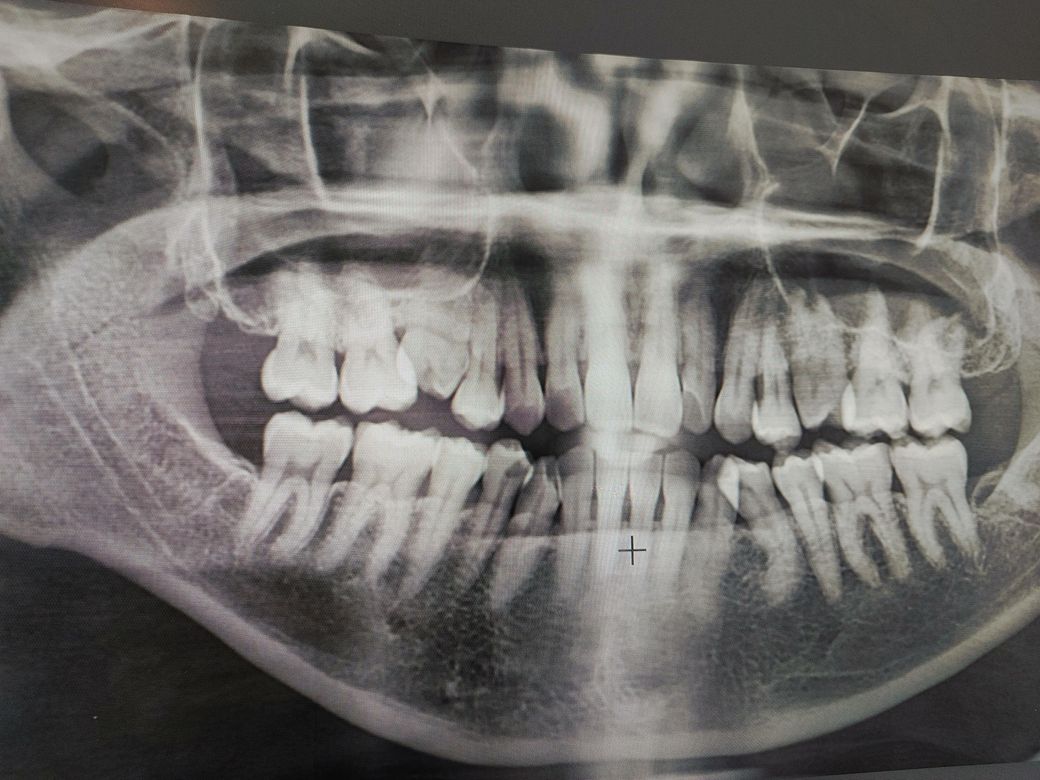

우측 상단 어금니 시림 증상 질문입니다.

오늘 시린증상이 심해져서 다시 동네치과를 가니 여전히 겉으로는 문제가 없고. 다만 어금니에 충격이 가해지고 치아 신경에 문제가 생긴거라면 신경치료가 필요할수는 있다. 다만 턱을 크게 벌려야 하기 때문에 턱부터 치료해야한다. 라는 소견만 듣고 왔습니다.

• 1번 째 사진